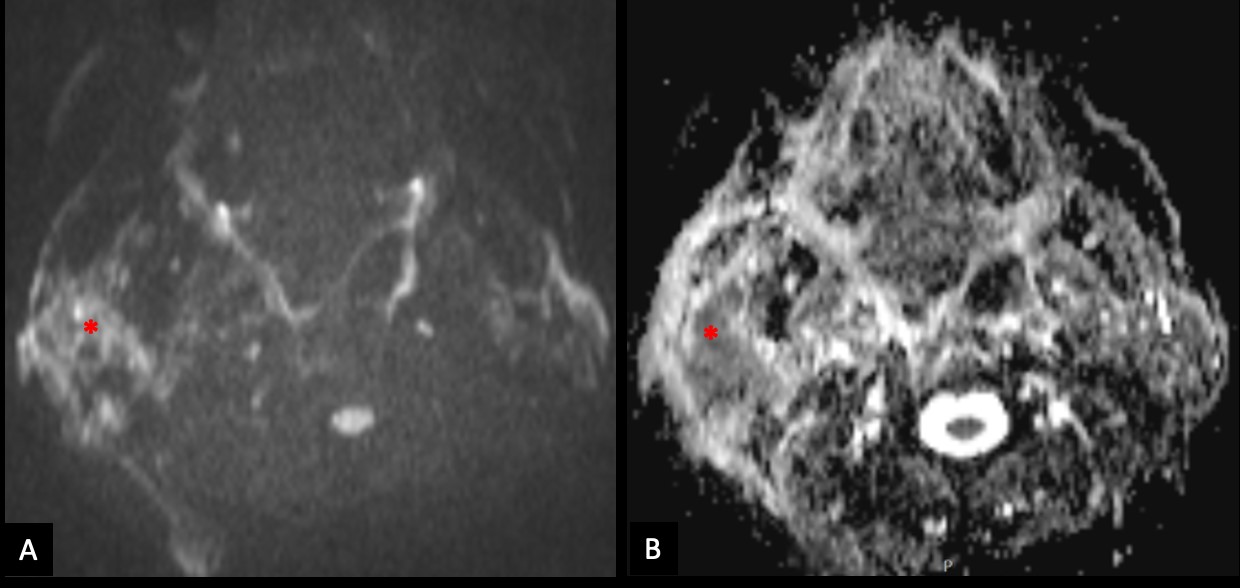

The lesion also revealed restricted diffusion, with an ADC value of 0,858 x 10-3 mm2/s (Fig. 4). Additionally, a more focal nodular and irregular area was evident in the superficial parotid lobe. There was also a noticeable infiltration of the adjacent fat planes and skin, invasion of the right masseter muscle, and extension of the lesion to the submandibular space without the involvement of the right submandibular gland (both submandibular glands were atrophic). The right facial nerve showed a moderate high signal on T2-weighted images and post-contrast hyperenhancement that was perceptible in its path up to the stylomastoid foramen, which was a cause of concern regarding perineural spread (Fig. 5). Retromandibular vein thrombosis was visible. An increased number of lymph nodes was present in all right cervical levels, the largest node measuring 11 mm (in greater diameter), some of them showing round morphology and central areas of necrosis. There were no signs of mandibular invasion or other suspicious bone lesions. CT also excluded signs of lung metastases. Ultrasound-guided fine needle aspiration of the right parotid lesion was performed, demonstrating involvement of the parotid parenchyma by a malignant tumor with a nest pattern constituted by epithelioid cells with eosinophilic cytoplasm and atypical nuclei, with evident nucleolus and frequent mitoses. Comedonecrosis-type tumor necrosis areas, as well as lymphatic and vascular invasion were observed. The findings were compatible with a salivary duct carcinoma (SDC), with expression of androgen receptors. The management options were discussed in a multidisciplinary group meeting and with the patient. Due to the extension of the neoplastic lesion and the potential morbidity associated with the surgical procedure that would preclude a complete resection, radiotherapy and antiandrogen therapy were chosen.

Figure 4: The right parotid lesion shows moderate restricted diffusion (*), with high signal on diffusion-weighted image with b value of 800s/mm2 (A) and low signal on apparent diffusion coefficient map (B).